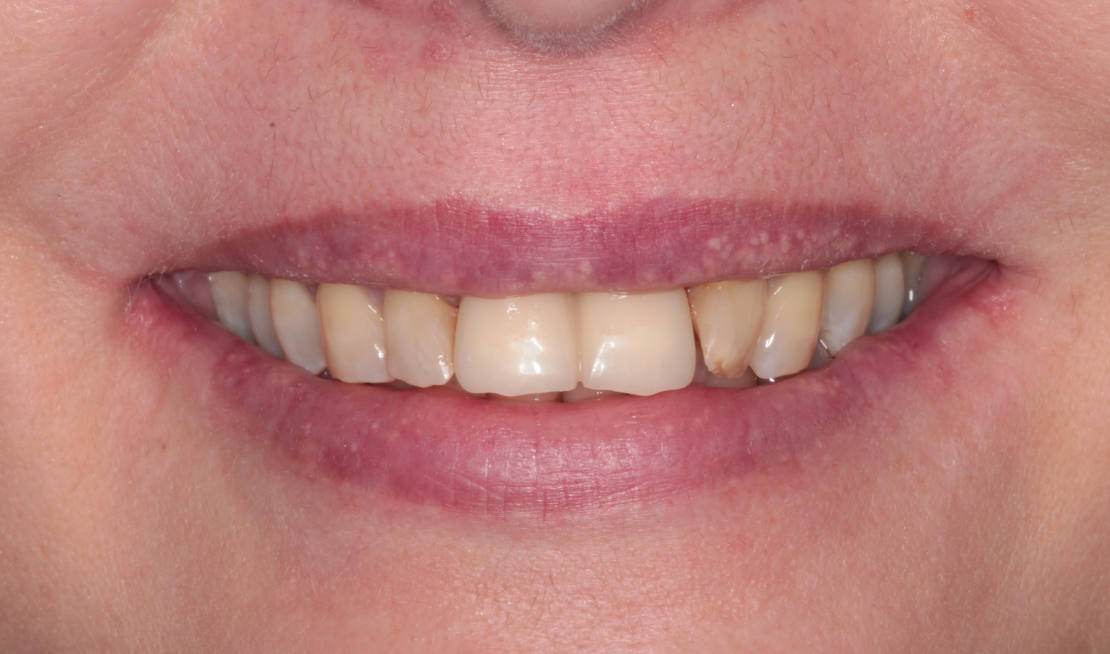

Kontrola po 10 dňoch (obr. 15–19).